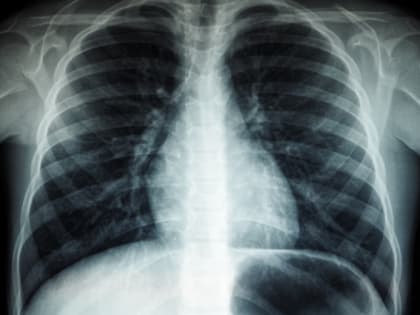

Искусственный интеллект поможет магаданским врачам-рентгенологам

В Магаданской областной больнице запустили программу с искусственным интеллектом «Цельс», который умеет в автоматическом режиме читать маммографические снимки.